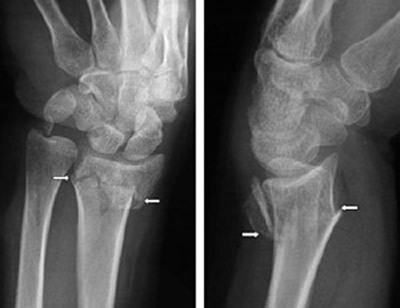

Prijelom radijusa nastaje na mjestu koje je 2-3 cm udaljeno od ručnog zgloba. Nastaje prilikom pada na ispruženu ruku gdje je ručni zglob u dorzalnoj fleksiji, a podlaktica u pronaciji. To je tzv. Collesova fraktura gdje je distalni fragment pomaknut prema dorzalno i radijus dobije izgled francuske vilice. Nasuprot ovom mehanizmu, pri padu na dorzum šake nastaje Smithova fraktura gdje je distalni fragment pomaknut prema volarno, oblik radijusa nalik je na bajonet.

Oko ručnog zgloba nastaje otok, bol i deformitet, ovisno o mehanizmu ozljede. Funkcije šake i prstiju su ograničeni zbog bolova. Gledano sprijeda, ruka je deformisana u vidu bajoneta zbog pomjeranja donjeg fragmenta upolje, unazad i naviše. Gledano sa strane, ruka je deformisana u vidu leđa od viljuške zbog pomjeranja donjeg fragmenta put dorzalno i proksimalno i pomjeranja proksimalnog fragmenta palmarno.

- RTG